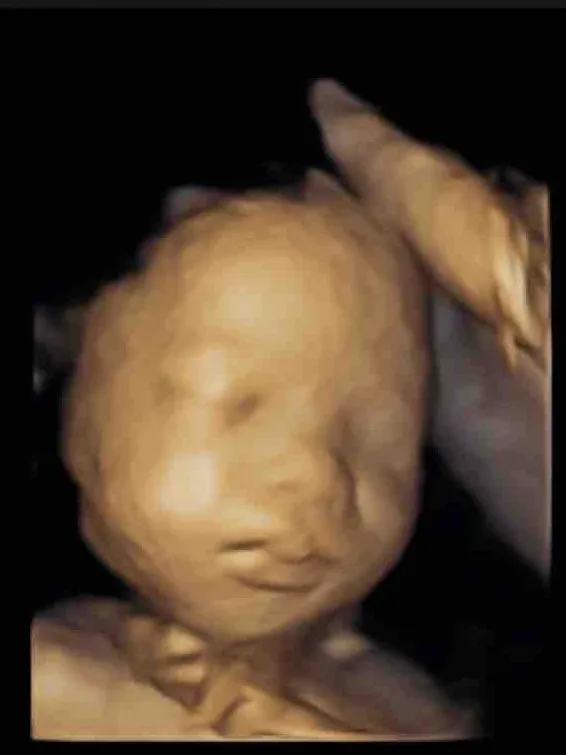

我人生的奇幻旅程已不能再那麼浪漫,傍晚超音波照出女兒的清晰輪廓,也告訴著我該是時候轉換身份,啟發更多後輩了。